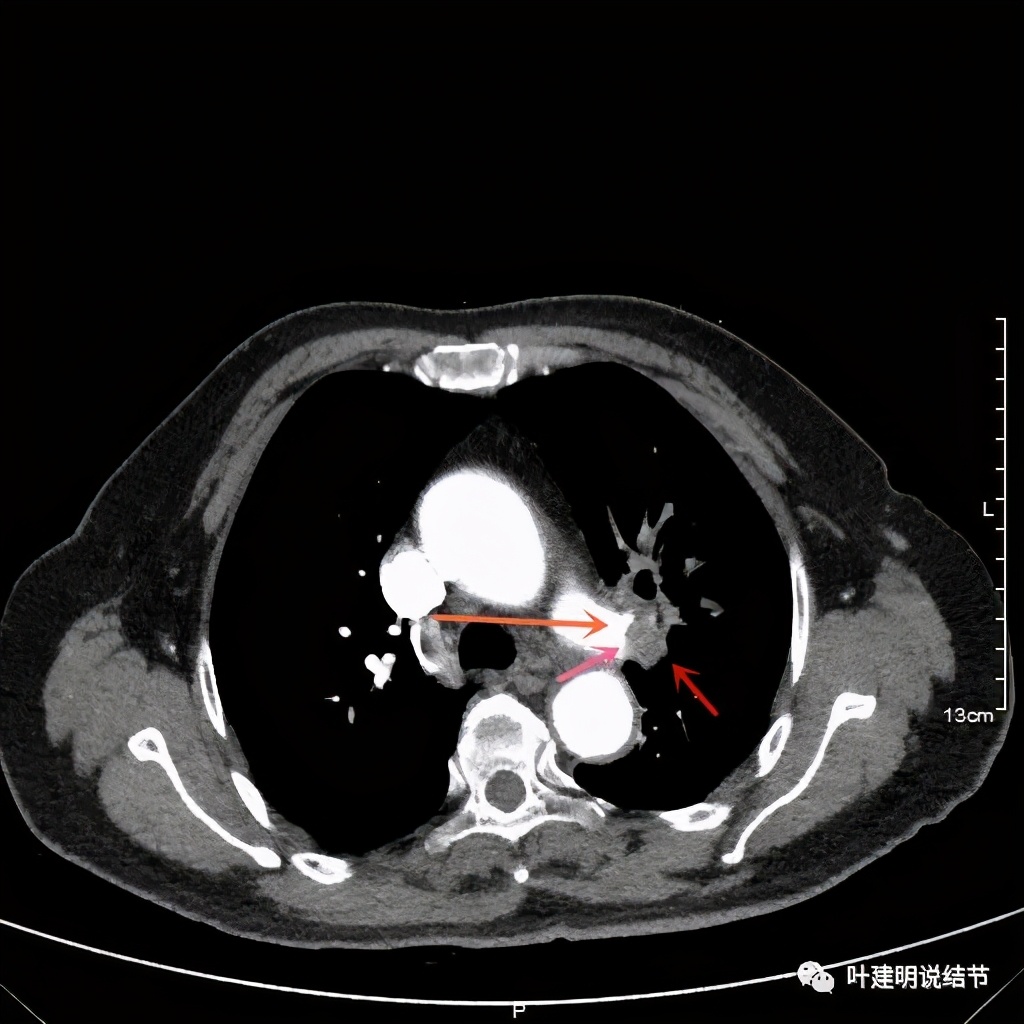

患者手术安排在2021.6.21进行,手术组先胸腔镜进胸探查有无胸壁转移及胸水,评估手术切除的可能性,并在镜下游离下肺韧带、清扫纵隔淋巴结,解剖游离上肺静脉,并将左肺动脉主干游离出来并套阻断带备用,以防解剖过程中出血时控制肺动脉出血。因肺门部原肿瘤部位仍与叶间动脉及上叶支气管、肺动脉分支等愈着紧密:

上图红色箭头示肿瘤,桔色示肺动脉及其分支,仍关系紧密

上图示肺动脉仍与软组织影关系密切,没有间隙可分开

上图示肺动脉与肿瘤的关系仍紧密

上两图示叶间肺动脉的上缘与肿瘤没有界限